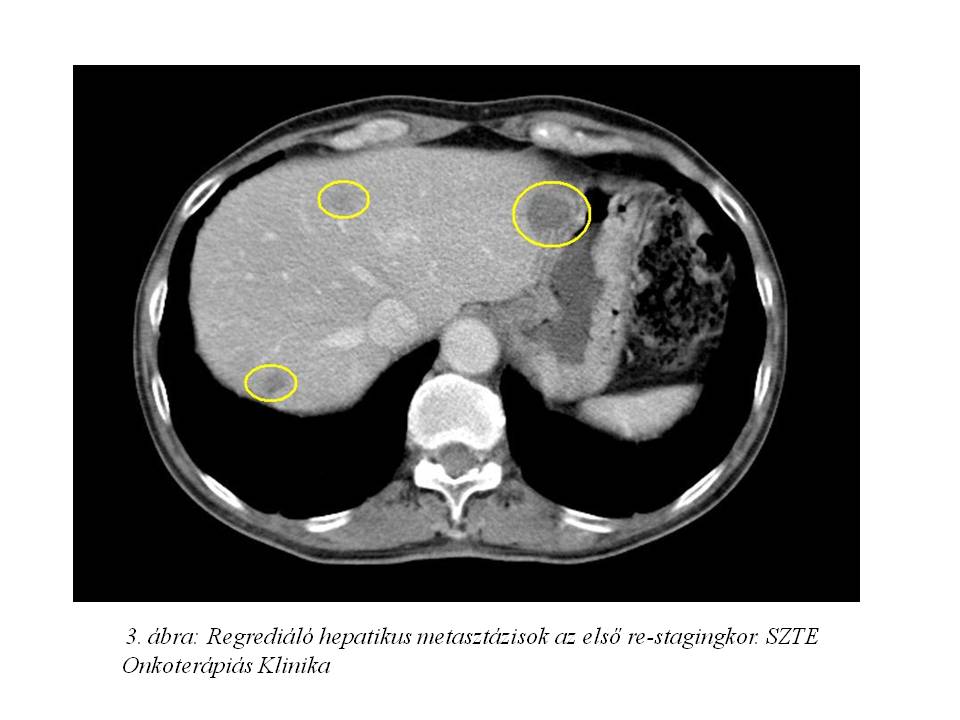

Palliatív onkológiai kezelésként FOLFIRI-bevacizumab immunochemotherápia indult 2011.07.05-től. Az első re-stagingkor (3. ábra, 4. ábra) már parciális remissziót észleltünk (46% csökkenés) mind a primer tumor, mind a tüdő-, mind a máj metasztázisok méretében. 2011.10.18-ára (5. ábra, 6. ábra) a regresszió tovább nőtt (59%). A kezelés mellékhatásaként, az irinotecan infúziót követően jelentkező orrváladékozást (irinotecan okozta specifikus parasympatikus tünet) a további kezelések során sc. atropinnal premedikáltuk, míg Gr.I. postinfúziós vénagyulladását lokálisan kezeltük. A 30. ciklustól a kezeléseket követően émelygés jelentkezett, mely otthon szedett ondansetron hatására megszűnt. Az 53. ciklust követően Gr.III-as hasmenés, exsiccatio és Gr.IV. neutropénia miatt hospitalizálás vált szükségessé. Empirikusan indított intravénás, széles spektrumú, kombinált antibiotikum, sc. filgrastim kezelés, parenterális folyadék-, és elektrolit pótlás hatására állapota rendeződött. Kezelését ezt követően folytattuk, de az észlelt súlyos mellékhatások miatt 25%-os redukciót alkalmaztunk a kemoterápiás szerek dózisában.